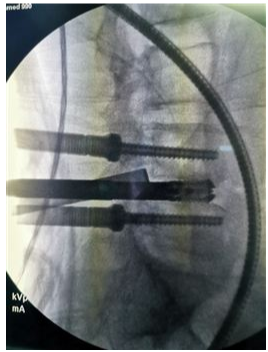

奧蘇本UBE技術概UBE技術即單側雙通道內(nèi)鏡技術(Unilateral Biportal Endoscopy Technique),適用于頸椎、胸椎、腰椎的退行性病變。與椎間孔鏡的單通道不同,該技術通常建立兩個通道,一個為觀察通道,一個為器械操作通道。觀察通道一般會用到0°或30°UBE內(nèi)鏡,操作通道使用UBE專器械,如UBE刮匙、磨鉆(UBE內(nèi)鏡磨頭)、UBE內(nèi)鏡刨刀、UBE內(nèi)鏡消融電極、UBE椎板咬骨鉗、UBE髓核鉗、UBE神經(jīng)拉鉤等。UBE技術的專用器械包,通過UBE技術還可以完成鏡下融合手術。

該技術開展脊柱手術時,克服了中心管狹窄、側管狹窄和椎間孔狹窄的局限。手術入路角度范圍廣,在不損傷脊柱結構完整性的前提下,有效地對椎管進行了周向和局部減壓,保留了肌肉韌帶附著通過肌間間隙,保護背支內(nèi)側支,從而防止牽張損傷。這種內(nèi)窺鏡入路允許從對側后入路和孔外入路(椎旁孔外入路)進入孔,為治療所有類型的狹窄提供了靈活性,因此,UBE技術作為一種微創(chuàng)的融合方法,具有極強的實用性。